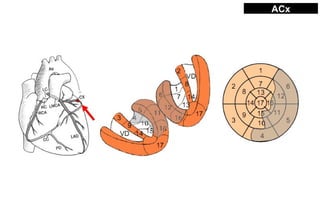

IAM PARED INFERIOR

• Dominancia se refiere a arteria que da DP

• Pared inferior es irrigada por:

– ACD 80-85%: dominancia derecha

– ACx 15%: dominancia izquierda

– 10% codominancia

– Compromiso de pared posterior y/o lateral con ambas dominancias

• IAM de pared inferior es importante discriminar RCA (proximal/distal)

versus ACx para implicancia terapeutica si compromiso de VD

– Algoritmos publicados, Fiol 2004, Gregg 2011

PARED INFERIOR ACx

•INFERO-LATERAL más común ACx

•IAM ACx 30% no manifestación EKG

•Más raro que de STE que RCA

•INFERIOR por ACx

-D1 iso-eléctrica o STE

-STE >0,5mm en V5-V6

-STE pared lateral escaso (aVL)

-STE II>III ACx dominante S97 E90